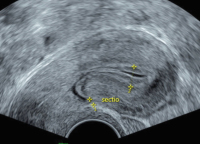

Ultraschall-Serometra

Abbildung 8: Markante Sectionarbe am nichtschwangeren Uterus am 10. Zyklustag, Darstellung mit NaCl. Die residuale myometriale Dicke (RMT) beträgt 3 mm.

Keywords: GynäkologieKochsalzlösungSectionarbeSerometraSonographieUltraschallUterus